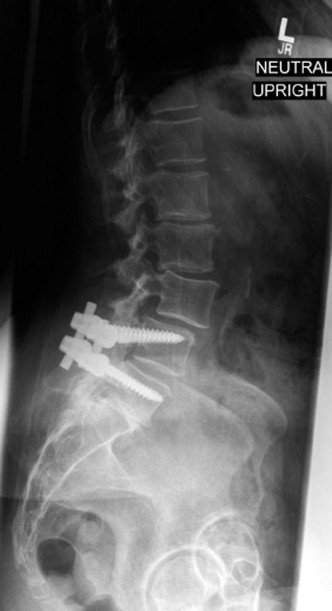

CASE 1 A 63-year-old male sustained a hyperextension injury to his neck while diving into a pool. Upon presentation, he reports decreased sensation in his hands and decreased strength in his arms and wrists, but no lower extremity complaints. On motor examination, he has 5/5 strength in his deltoids and elbow flexors and 4/5 strength in the elbow extensors, wrist extensors, and finger flexors. Lower extremity motor examination is normal. Sensation is decreased to light touch in both hands. Otherwise his sensation is preserved. Images of his cervical spine are shown in Figures 1–1 to 1–3.

Figure 1–1

The correct answer is (B). The clinical scenario describes a patient with central cord syndrome (CCS). CCS continues to be the most common incomplete spinal cord injury accounting for 15.7% to 25% of all spinal cord injuries. The characteristic presentation is an extension moment injury in a previously spondylotic and stenotic spine. Figures 1–1 to 1–3 demonstrate a spondylotic spine with central narrowing and CSF effacement that is worst at the C3–4 level. Bleeding, edema, and/or Wallerian degeneration lead to damage of the lateral corticospinal tract which is the main descending motor tract in the spinal cord. The more central anatomic position of the homunculus to the upper extremities places them at greater risk than those to the lower extremities. As such, injury to the lateral corticospinal tract is characterized by upper more than lower extremity involvement and motor deficits being more pronounced than sensory deficits.